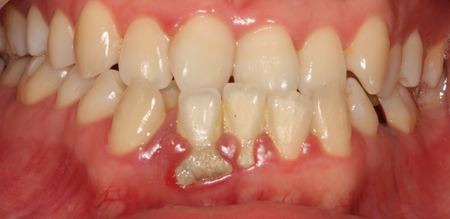

치주치료 전후사진

B

A

치주염 단계별 증상

건강한 상태

치아 주위의 잇몸이 핑크색을 띄며, 잇몸에서 피가 나지 않음.

스케일링을 6개월 ~ 1년 주기로 받고 올바른 칫솔질로 건강한 치주 조직을 유지

치은염 (초기~중기)

치아 주위의 잇몸이 붉게 부어 있으며, 칫솔질 등을 할 때 피가 남.

스케일링 주기의 조절이 필요할 수 있으며, 올바른 칫솔질을 시행하여야 함.

치주염 (중기~말기)

주기적으로 잇몸이 붓고 피가 나며, 욱씬하거나 우리한 통증이 나타남.

치주치료 및 정도에 따라 치주수술(잇몸수술)이 필요함. 향후 관리 정도에 따라 3~6개월 간격으로 내원하여 유지치료를 시행하여야 함.

치주염 (말기)

잇몸이 항상 부어 있으며, 이가

흔들리는 정도가 점점 심해짐.

치주치료가 필요하며, 정도에 따라 치아를 발치하여야 할 수 있음.